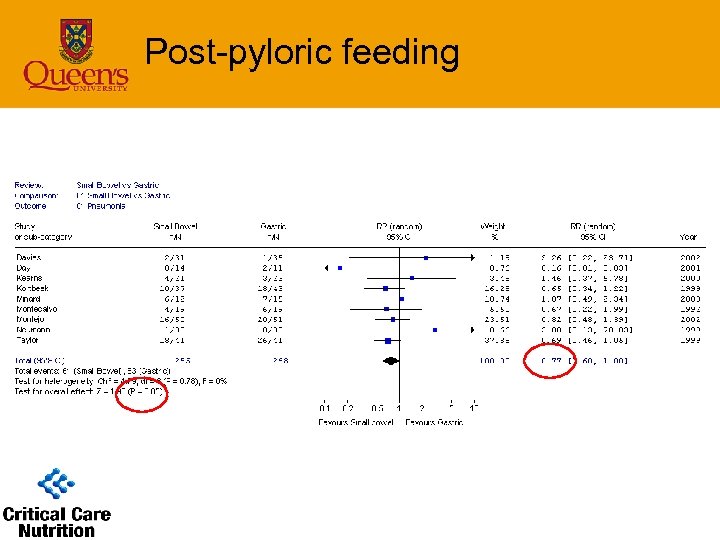

Post-pyloric feeding • Infections – pneumonia (9 studies) • 8 clinical criteria; 1 bronchoscopy • SB feeding associated with reduced pneumonia – RR=0. 77(0. 60 -1. 0), p=0. 05 – 23% risk reduction • With Taylor study removed – RR=0. 83(0. 6 -1. 15), p=0. 3

Post-pyloric feeding • Infections – pneumonia (9 studies) • 8 clinical criteria; 1 bronchoscopy • SB feeding associated with reduced pneumonia – RR=0. 77(0. 60 -1. 0), p=0. 05 – 23% risk reduction • With Taylor study removed – RR=0. 83(0. 6 -1. 15), p=0. 3

Post-pyloric feeding

Post-pyloric feeding